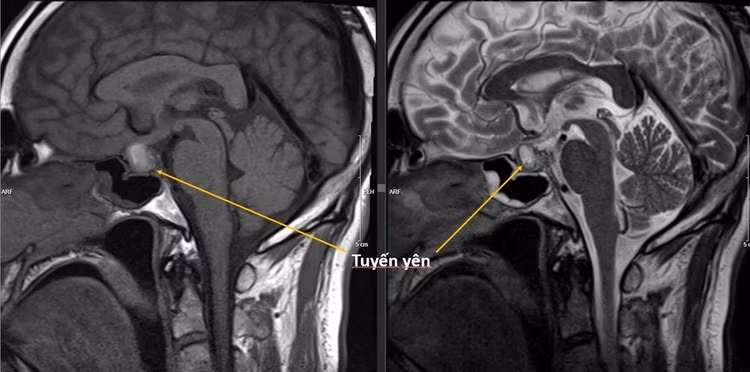

Tuyến yên là một tuyến nội tiết nằm ở trong hố yên của vùng nền sọ, xương bướm. Mặc dù có kích thước chỉ bằng hạt đỗ, khoảng 8 - 10mm, nặng chỉ 0,5g, nhưng tuyến yên có vai trò rất quan trọng do nó chi phối chức năng của hầu hết các tuyến nội tiết trong cơ thể (tuyến giáp, tuyến thượng thận, tuyến vú, tuyến sinh dục...).

Hình ảnh u tuyến yên trên phim của bệnh nhân.

Đột quỵ tuyến yên là tình trạng u tuyến yên hoại tử chảy máu, chiếm 2 - 10% u tuyến yên nói chung, gặp nhiều hơn ở khối u có kích thước càng lớn. Nguyên nhân dẫn đến tình trạng này chưa rõ, nhiều tác giả cho rằng do bất thường của mạch máu trong tuyến yên, do u chèn ép vào động mạch yên trên.

U tuyến yên hoại tử, chảy máu, phù tăng nhanh dẫn đến tăng áp lực trong hố yên, có thể tới 45 - 50mmHg, chèn ép xung quanh, gây ra: (1) chèn ép xoang hang, gây ra đau đầu dữ dội, buồn nôn, thậm chí nôn vọt (chiếm tới 95% trường hợp); (2)chèn ép các dây thần kinh trong xoang hang, cạnh hố yên (dây II, III, IV, V, VI), gây ra sụp mi, lác, giảm thị lực, nhìn đôi (chiếm 70-75% trường hợp); (3) Chèn ép động mạch cảnh trong có thể gây ra nhồi máu não; (4) Chèn ép tuyến yên lành dẫn đến suy tuyến yên (chiếm 70% trường hợp, hay gặp nhất là suy tuyến thượng thận) dẫn đến tụt huyết áp, hạ đường huyết, rối loạn điện giải, hôn mê thậm chí tử vong.